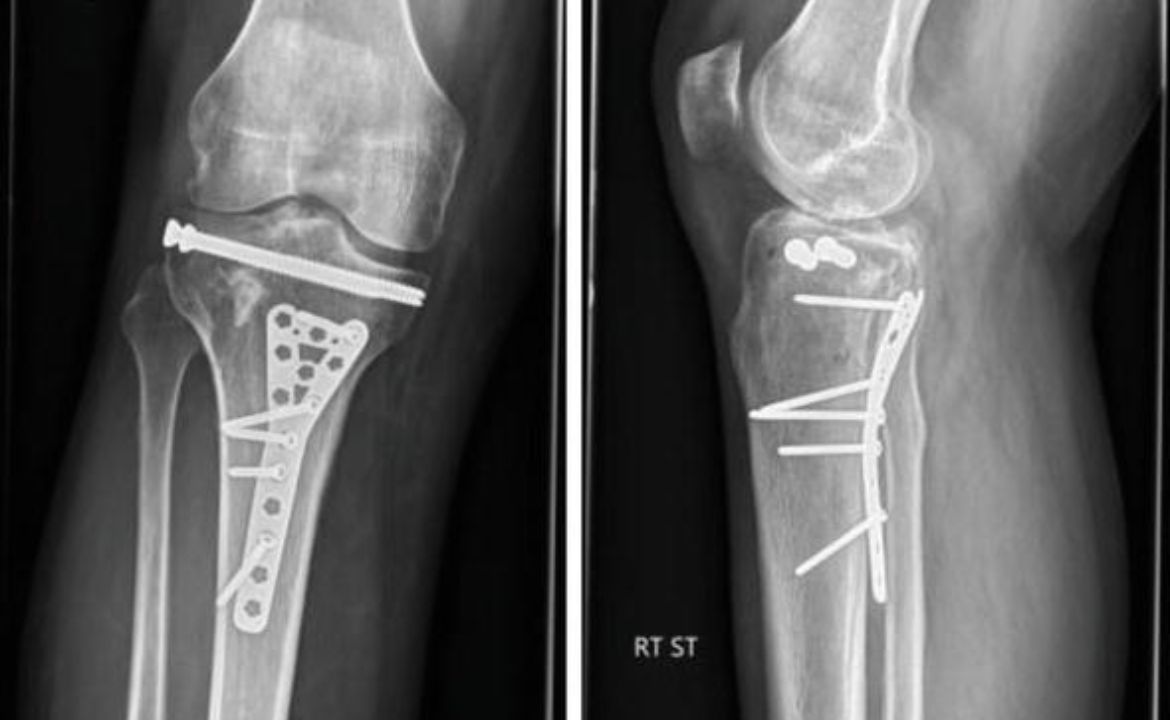

The tibial plateau fracture represents one of the most challenging orthopedic injuries affecting the knee joint. This complex injury involves…